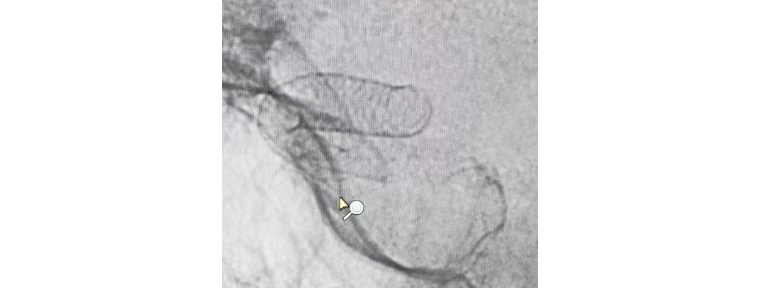

團(tuán)隊(duì)人員術(shù)前充分準(zhǔn)備,術(shù)中配合默契,支架順利釋放,造影觀察支架貼壁良好,瘤腔內(nèi)造影劑滯留,載瘤動(dòng)脈通暢,手術(shù)非常成功。術(shù)后兩天,患者平穩(wěn)出院,對(duì)治療效果很滿(mǎn)意。

支架成功釋放